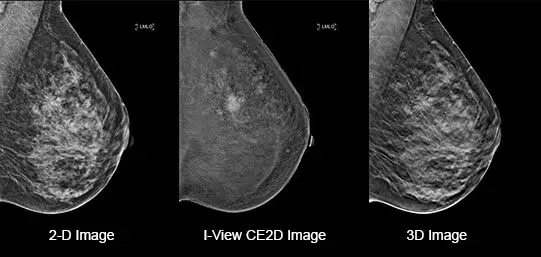

Capture a pair of high and low energy images in rapid succession. This enables visualization of areas with abnormal blood flow by subtracting the breast parenchyma background.